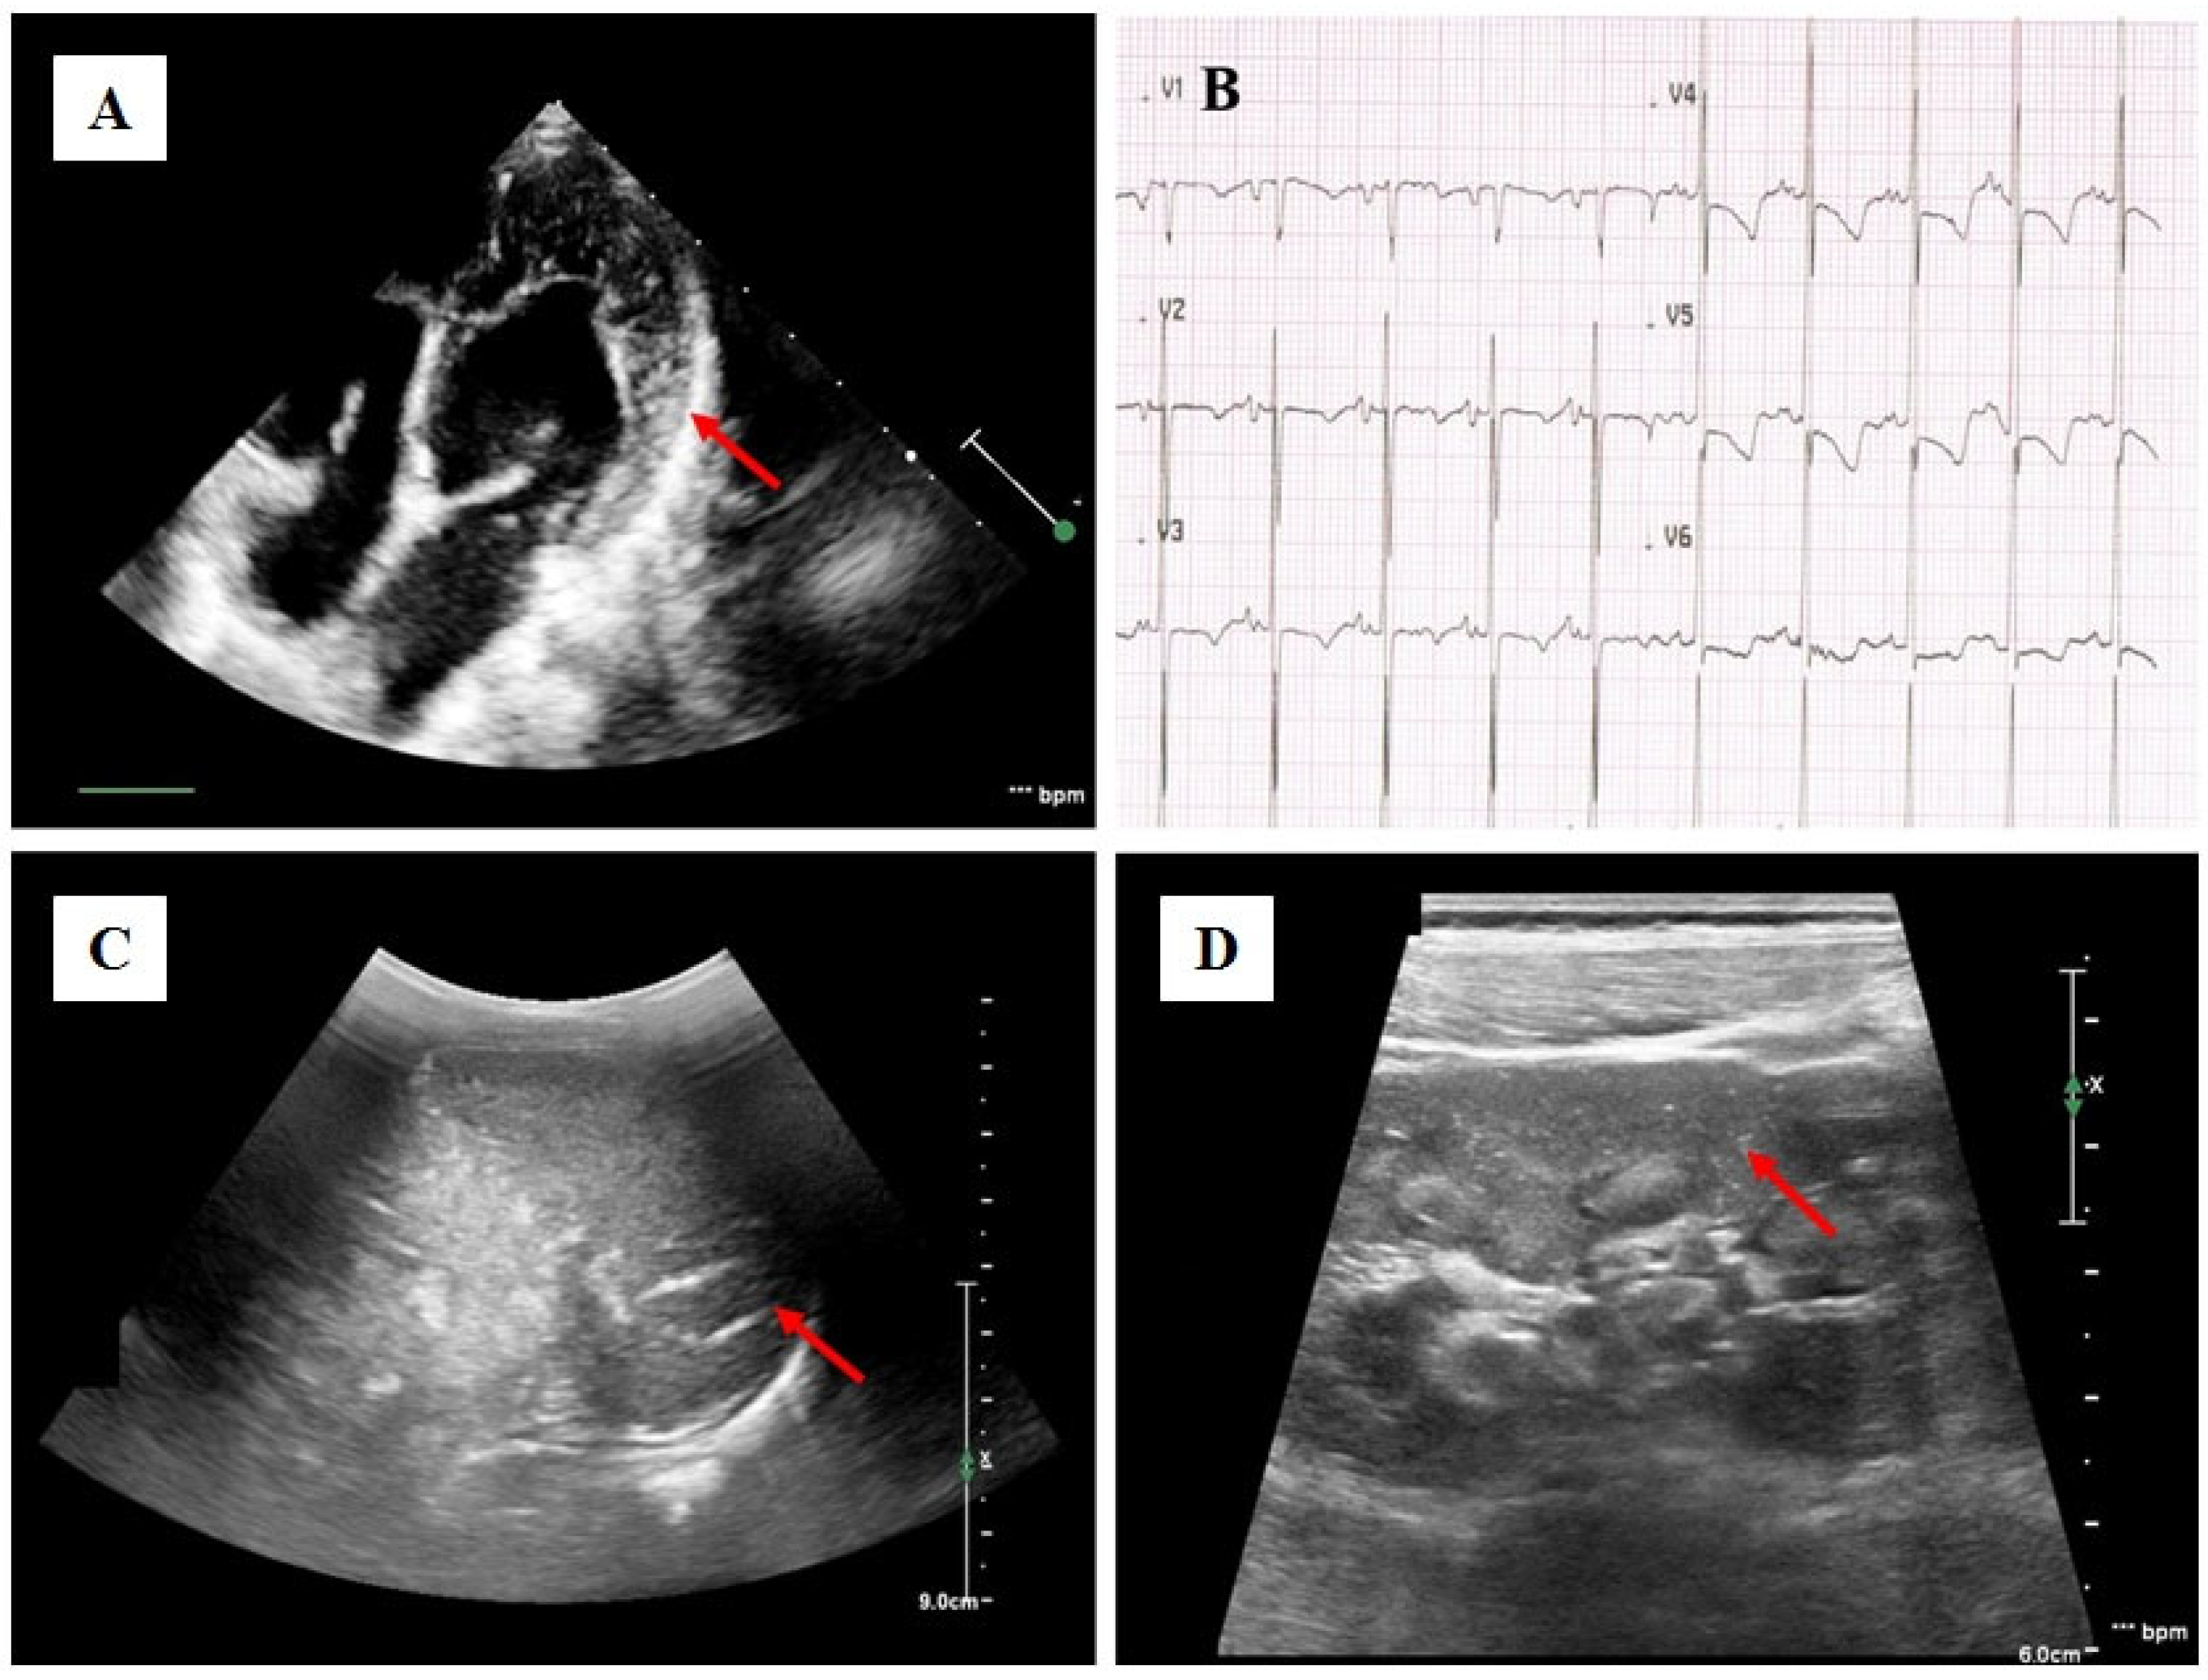

Case Presentation